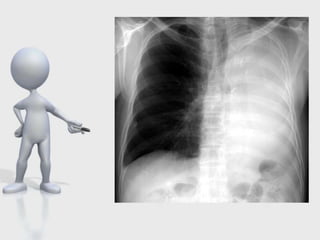

Complicaciónes postneumonectomía

SD. Postneumonectomia